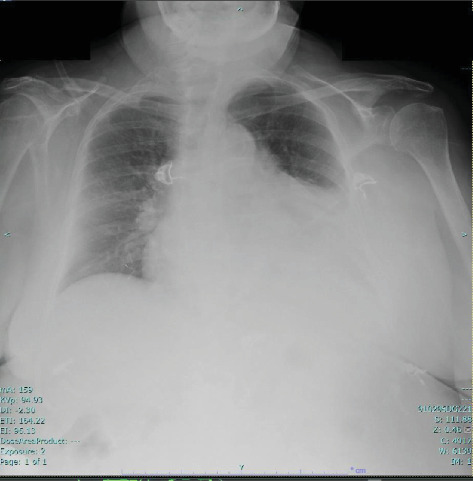

Hydralazine是一种常用的动脉血管扩张剂,用于治疗充血性心力衰竭和高血压,已知与药物性狼疮和抗中性粒细胞胞浆抗体(ANCA)相关血管炎(AAV)有关。药物诱导的AAV通常具有良好的长期预后,通常与心血管或眼部受累无关。与肼相关的心包炎病例以前未见报道。我们提出一个罕见的病例,涉及一名85岁的妇女长期服用肼,最初表现为急性大叶性肺炎。在住院期间,她出现心包炎、化脓和眼睛结膜炎,并伴有皮肤病变,包括面部丘疹、手指上的嫩嫩的大疱和背部的点疹。实验室结果与药物诱导的AAV一致,显示髓过氧化物酶和蛋白酶3抗体阳性。尝试诊断性心包穿刺失败。停用海拉嗪,她成功地用皮质类固醇治疗,免疫抑制耐受良好。随后,她康复出院。

Hydralazine, a commonly used arterial vasodilator for managing congestive heart failure and hypertension, is known to be associated with drug-induced lupus and, less frequently, antineutrophil cytoplasmic antibody (ANCA)-associated vasculitis (AAV). Drug-induced AAV typically carries a favorable long-term prognosis and is not commonly linked to cardiovascular or ocular involvement. Pericarditis cases associated with hydralazine have not been previously reported. We present a rare case involving an 85-year-old woman on long-term hydralazine therapy, initially presenting with acute lobar pneumonia. During her hospitalization, she developed pericarditis, chemosis, and conjunctivitis in her eyes, along with cutaneous lesions described as a maculopapular rash on her face, tender bullae on her digits, and a petechial rash on her back. Laboratory findings were consistent with drug-induced AAV, showing positive myeloperoxidase and proteinase 3 antibodies. An attempted diagnostic pericardiocentesis was unsuccessful. Hydralazine was discontinued, and she was successfully treated with corticosteroids and tolerated immunosuppression well. Subsequently, she recovered and was discharged from the hospital.